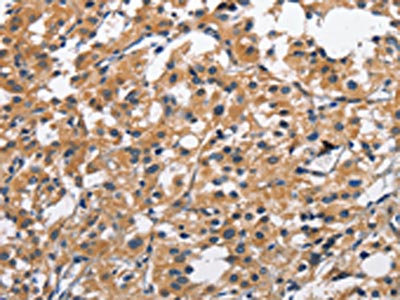

The image on the left is immunohistochemistry of paraffin-embedded Human thyroid cancer tissue using CSB-PA254797(CLEC2D Antibody) at dilution 1/70, on the right is treated with fusion protein. (Original magnification: ×200)

The image on the left is immunohistochemistry of paraffin-embedded Human liver cancer tissue using CSB-PA254797(CLEC2D Antibody) at dilution 1/70, on the right is treated with fusion protein. (Original magnification: ×200)